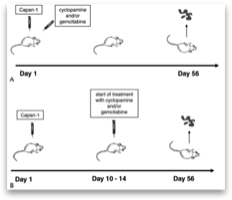

To test if the inhibition of Hedgehog signaling by cyclo- pamine identified in vitro also reduces tumor growth in vivo, we used a nu/nu nude mice xenograft model.

To determine whether growth inhibition by cyclopa- mine functions via blockade of Smo, we analyzed the PTCH1 expression in Capan-1 xenografts treated with cyclopamine. The application of cyclopamine led to a significant mRNA down- regulation of PTCH1 in the tumor tissue, indicating that cyclo- pamine treatment triggers a Hedgehog-related response in vivo. Moreover, a combined treatment with cyclopamine and the known antimetabolic agent gemcitabine resulted in a synergistic reduction of average tumor size compared with treatment of cy- clopamine or gemcitabine alone. Interestingly, previous studies indicated that growth inhibition of pancreatic cancer xenografts might be more pronounced when Hedgehog blockade was initiated concomitantly with the injection of tumor cells into nude mice. In our study, we could not confirm these findings.